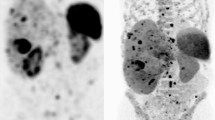

18F-FDG PET/CT is complementary to SSTR imaging in cases of high-grade and poorly differentiated GEP-NEN. It is typical for low-grade well-differentiated NENs to have little glucose metabolism, though, in 40% of these tumors, FDG uptake can be seen [54]. As dedifferentiation occurs, upregulation of glucose receptors and downregulation of SSTR occurs, termed a “flip-flop phenomenon” [4]. Significant inter and intra-tumoral variation occurs in patients with GEP-NENs. This led to the combined clinical use of both FDG and SSTR-PET to aid in characterizing tumor heterogeneity, risk stratification, and predicting tumor response to PRRT. A NETPET score was developed, combining imaging findings from 18F-FDG and SSTR-PET, which has shown promise as a prognostic biomarker and warrants investigation in future larger studies [55, 56].